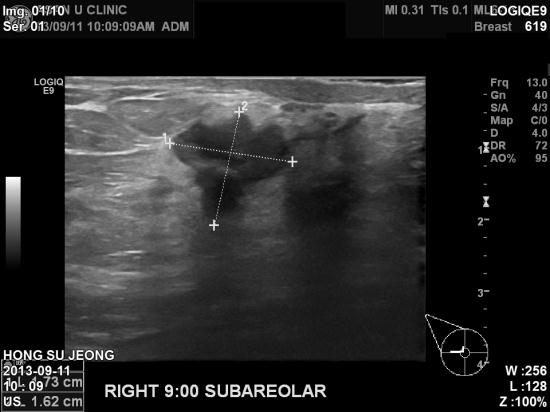

아산유외과 개원 후 23번째 유방암 진단.

1년전에도 공단검진상 정상이었다고 들었던 만 49세 여자분이

갑자기 우측유두근처에 혹이 만져져 내원하셨습니다.

조직검사상 1.73cm의 침윤성 유관암으로 진단되셨습니다.

규칙적으로 유방검사를 하시는 사이에 이렇게 진단된 유방암을 가리켜

간격암 "interval breast cancer"라고 합니다.

공단검진상 치밀유방이거나 몽우리가 만져지면 기다리지 말고 확인을 꼭 해봐야 합니다.